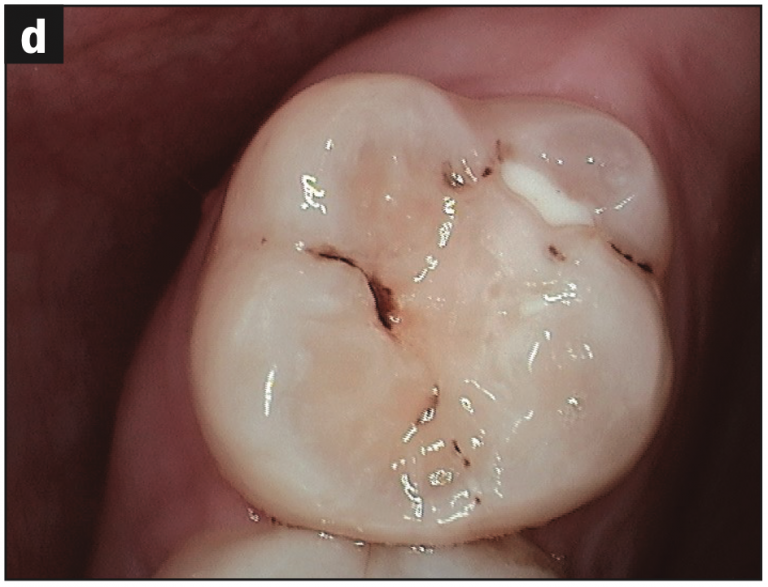

- Occlusal pitting (Figure 3a)

- Occlusal wear (Figures 3b and 3c)

- Decay (Figures 3b and 3d)